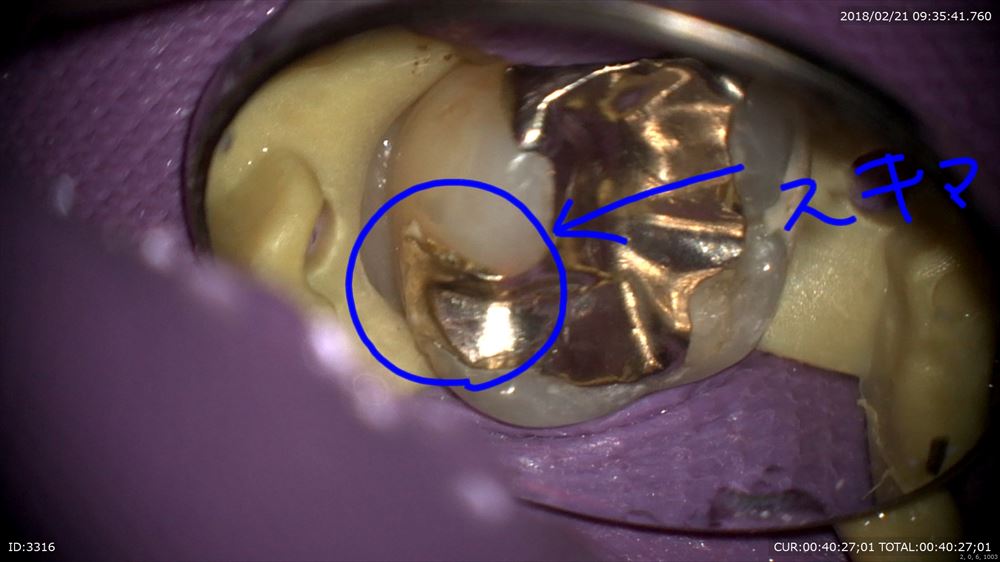

「他院で行った右上の歯が痛い」

神経が腫れて辛そうでした。歯科ドックで原因をお話しし本日精密根管治療スタート

この歯。やはり銀歯虫歯からの細菌侵入。隙間がありますね。

アップ。こんなに。。。